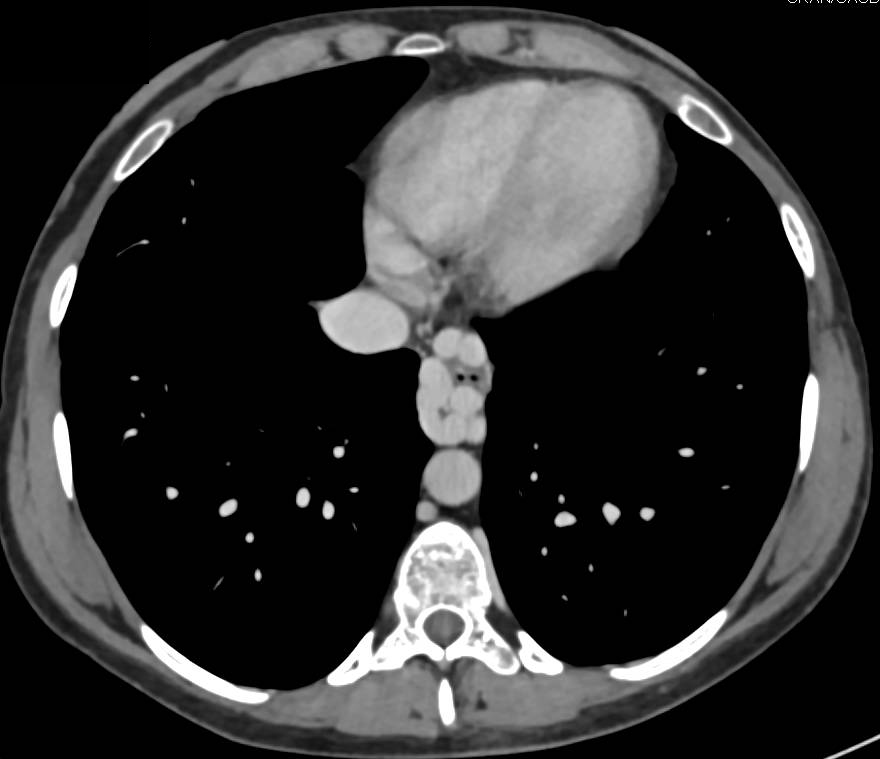

Cavernous Transformation of the Portal Vein